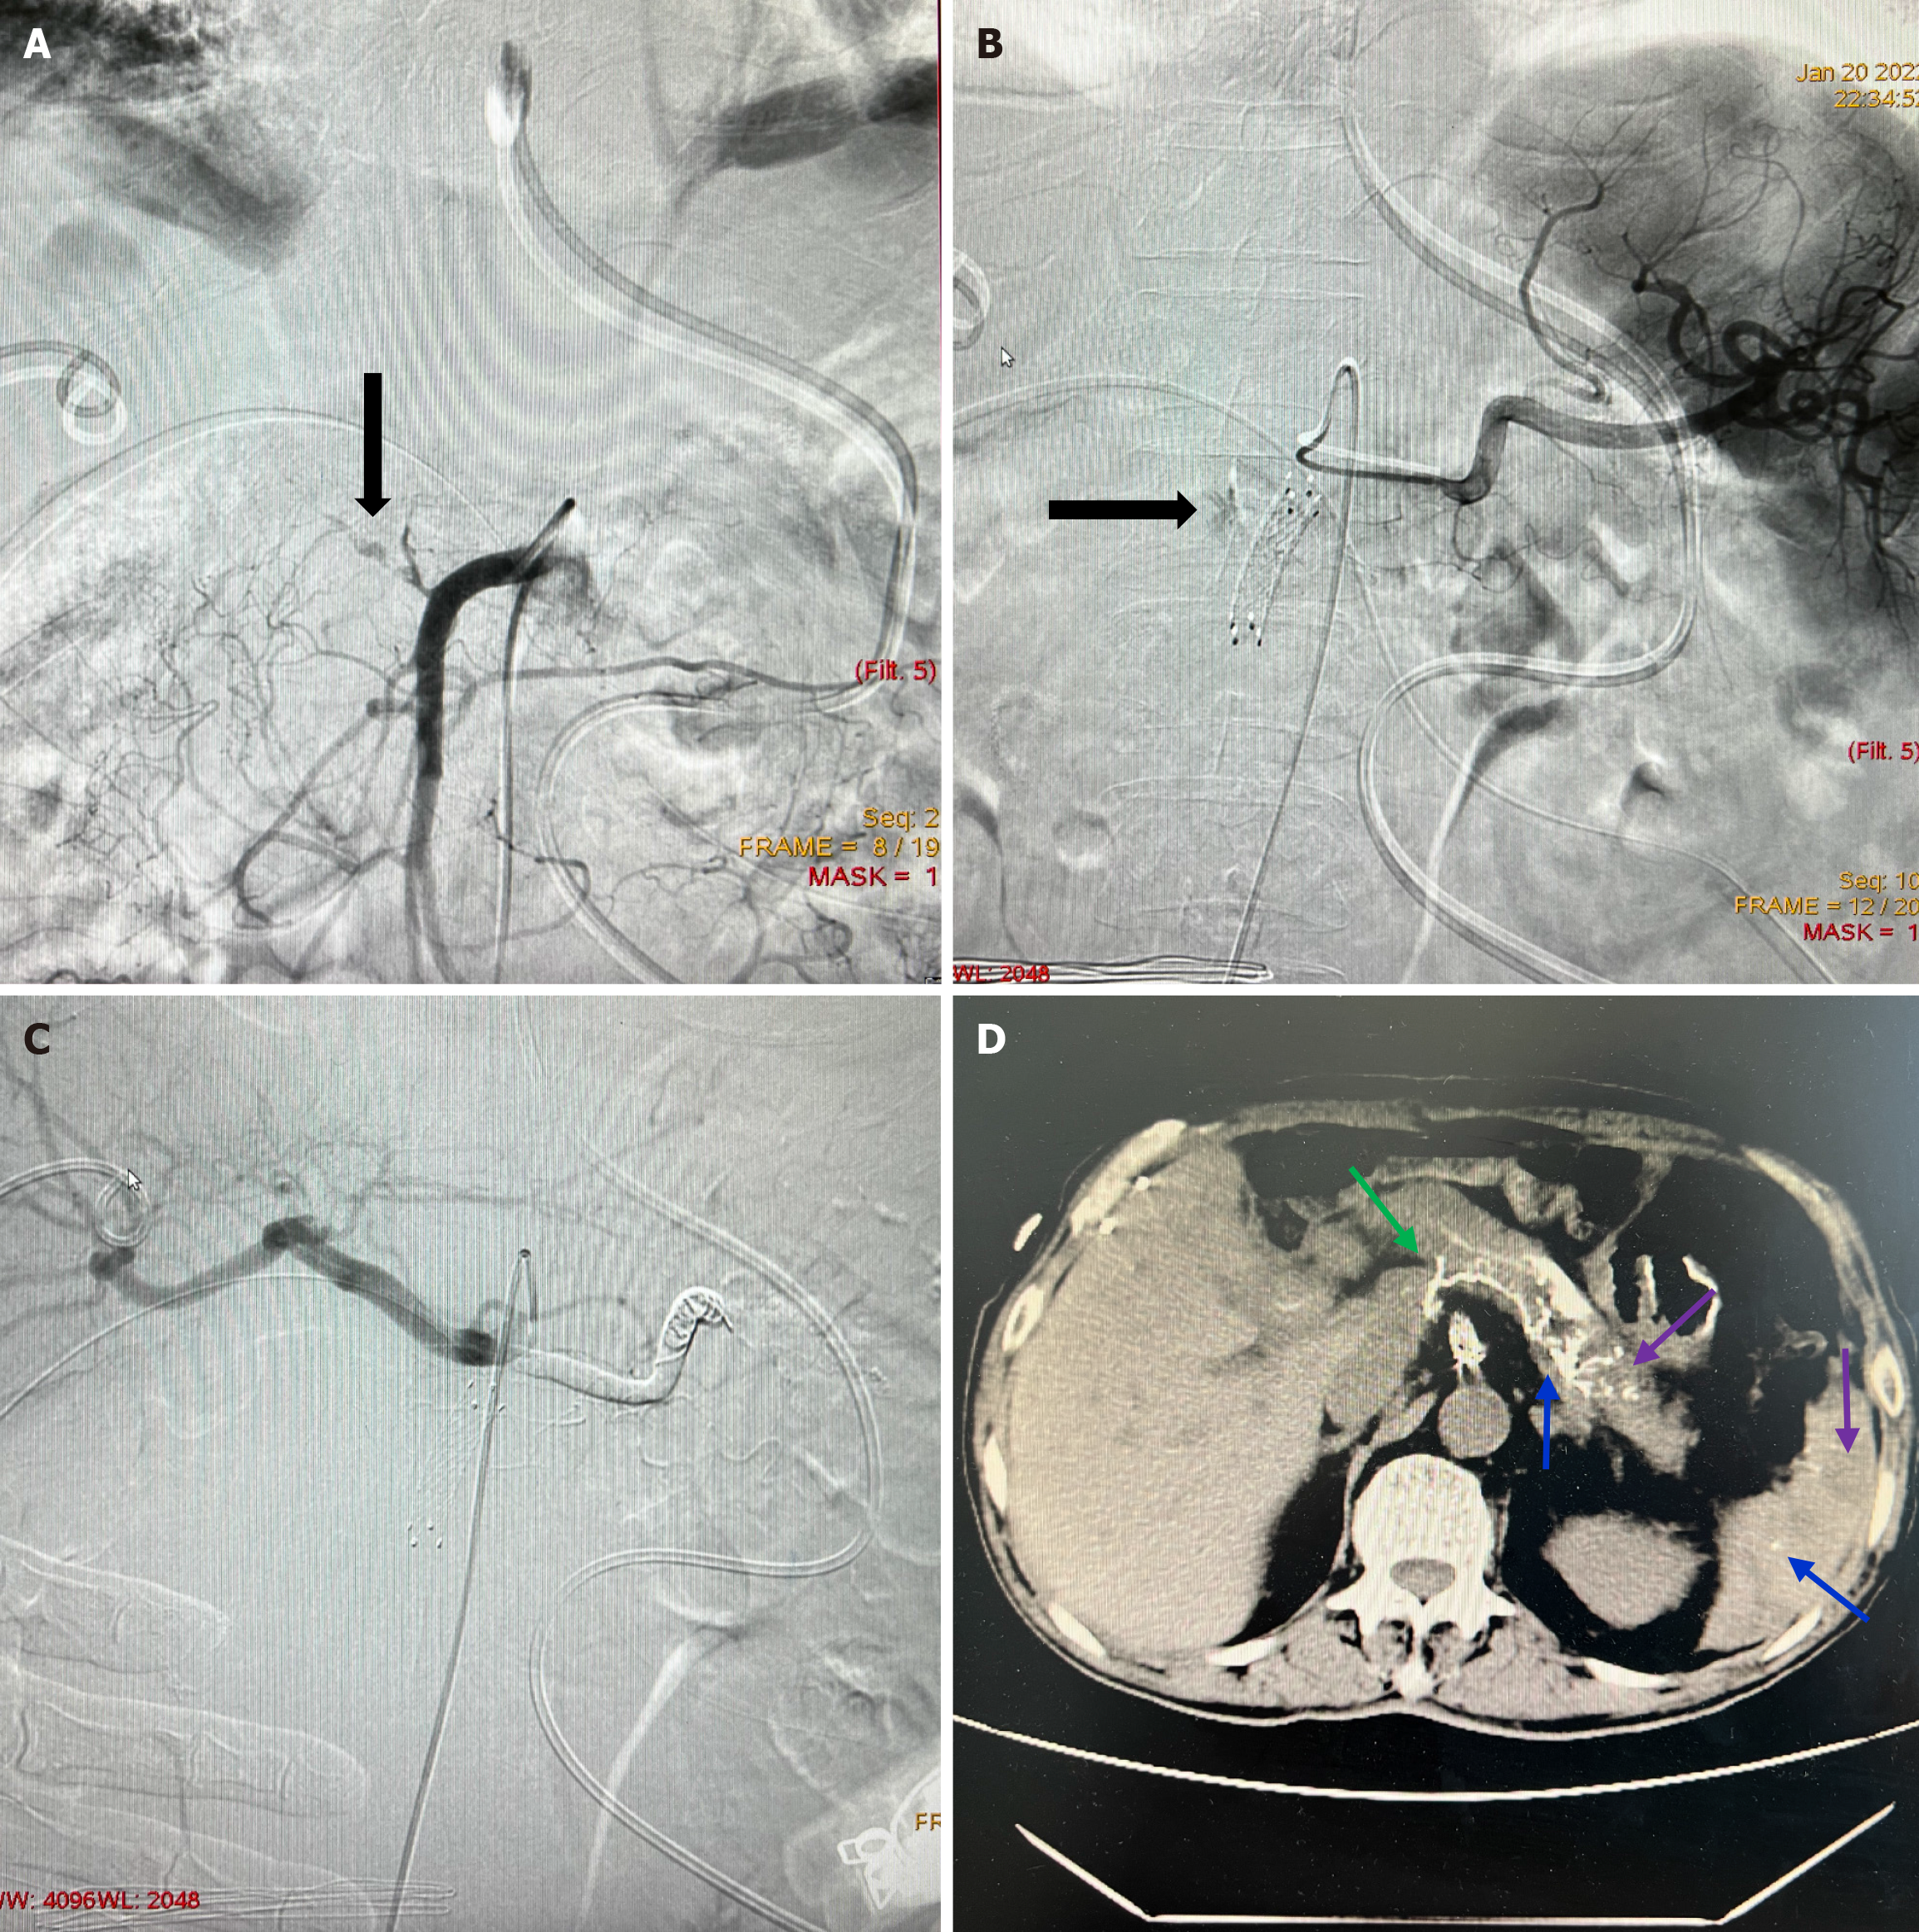

Figure 3 Hemorrhage occurring 19 days after pancreaticoduodenectomy for cholangiocarcinoma in a 68-year-old male patient.

A: Superior mesenteric artery angiography was performed, and extravasation of the contrast agent (black down arrow) was detected. Subsequently, covered stent implantation was performed; B: The patient experienced rebleeding 5 days after the initial endovascular treatment. Splenic artery angiography was performed, and extravasation of the contrast agent (black right arrow) was detected. Because of the tortuous origin of the splenic and bleeding arteries, superselective arterial embolization and covered stent implantation could not be performed successfully; C: Coil-assisted N-butyl cyanoacrylate (NBCA) embolization was performed successfully; D: NBCA deposits in the targeted bleeding lesion (green arrow) and target- and non-target-organ embolization (blue arrow) were observed in the subsequent imagological examination. Pancreatic and splenic small partial low-density regions (purple arrow) were asymptomatic and self-limited. The patient did not experience rebleeding.